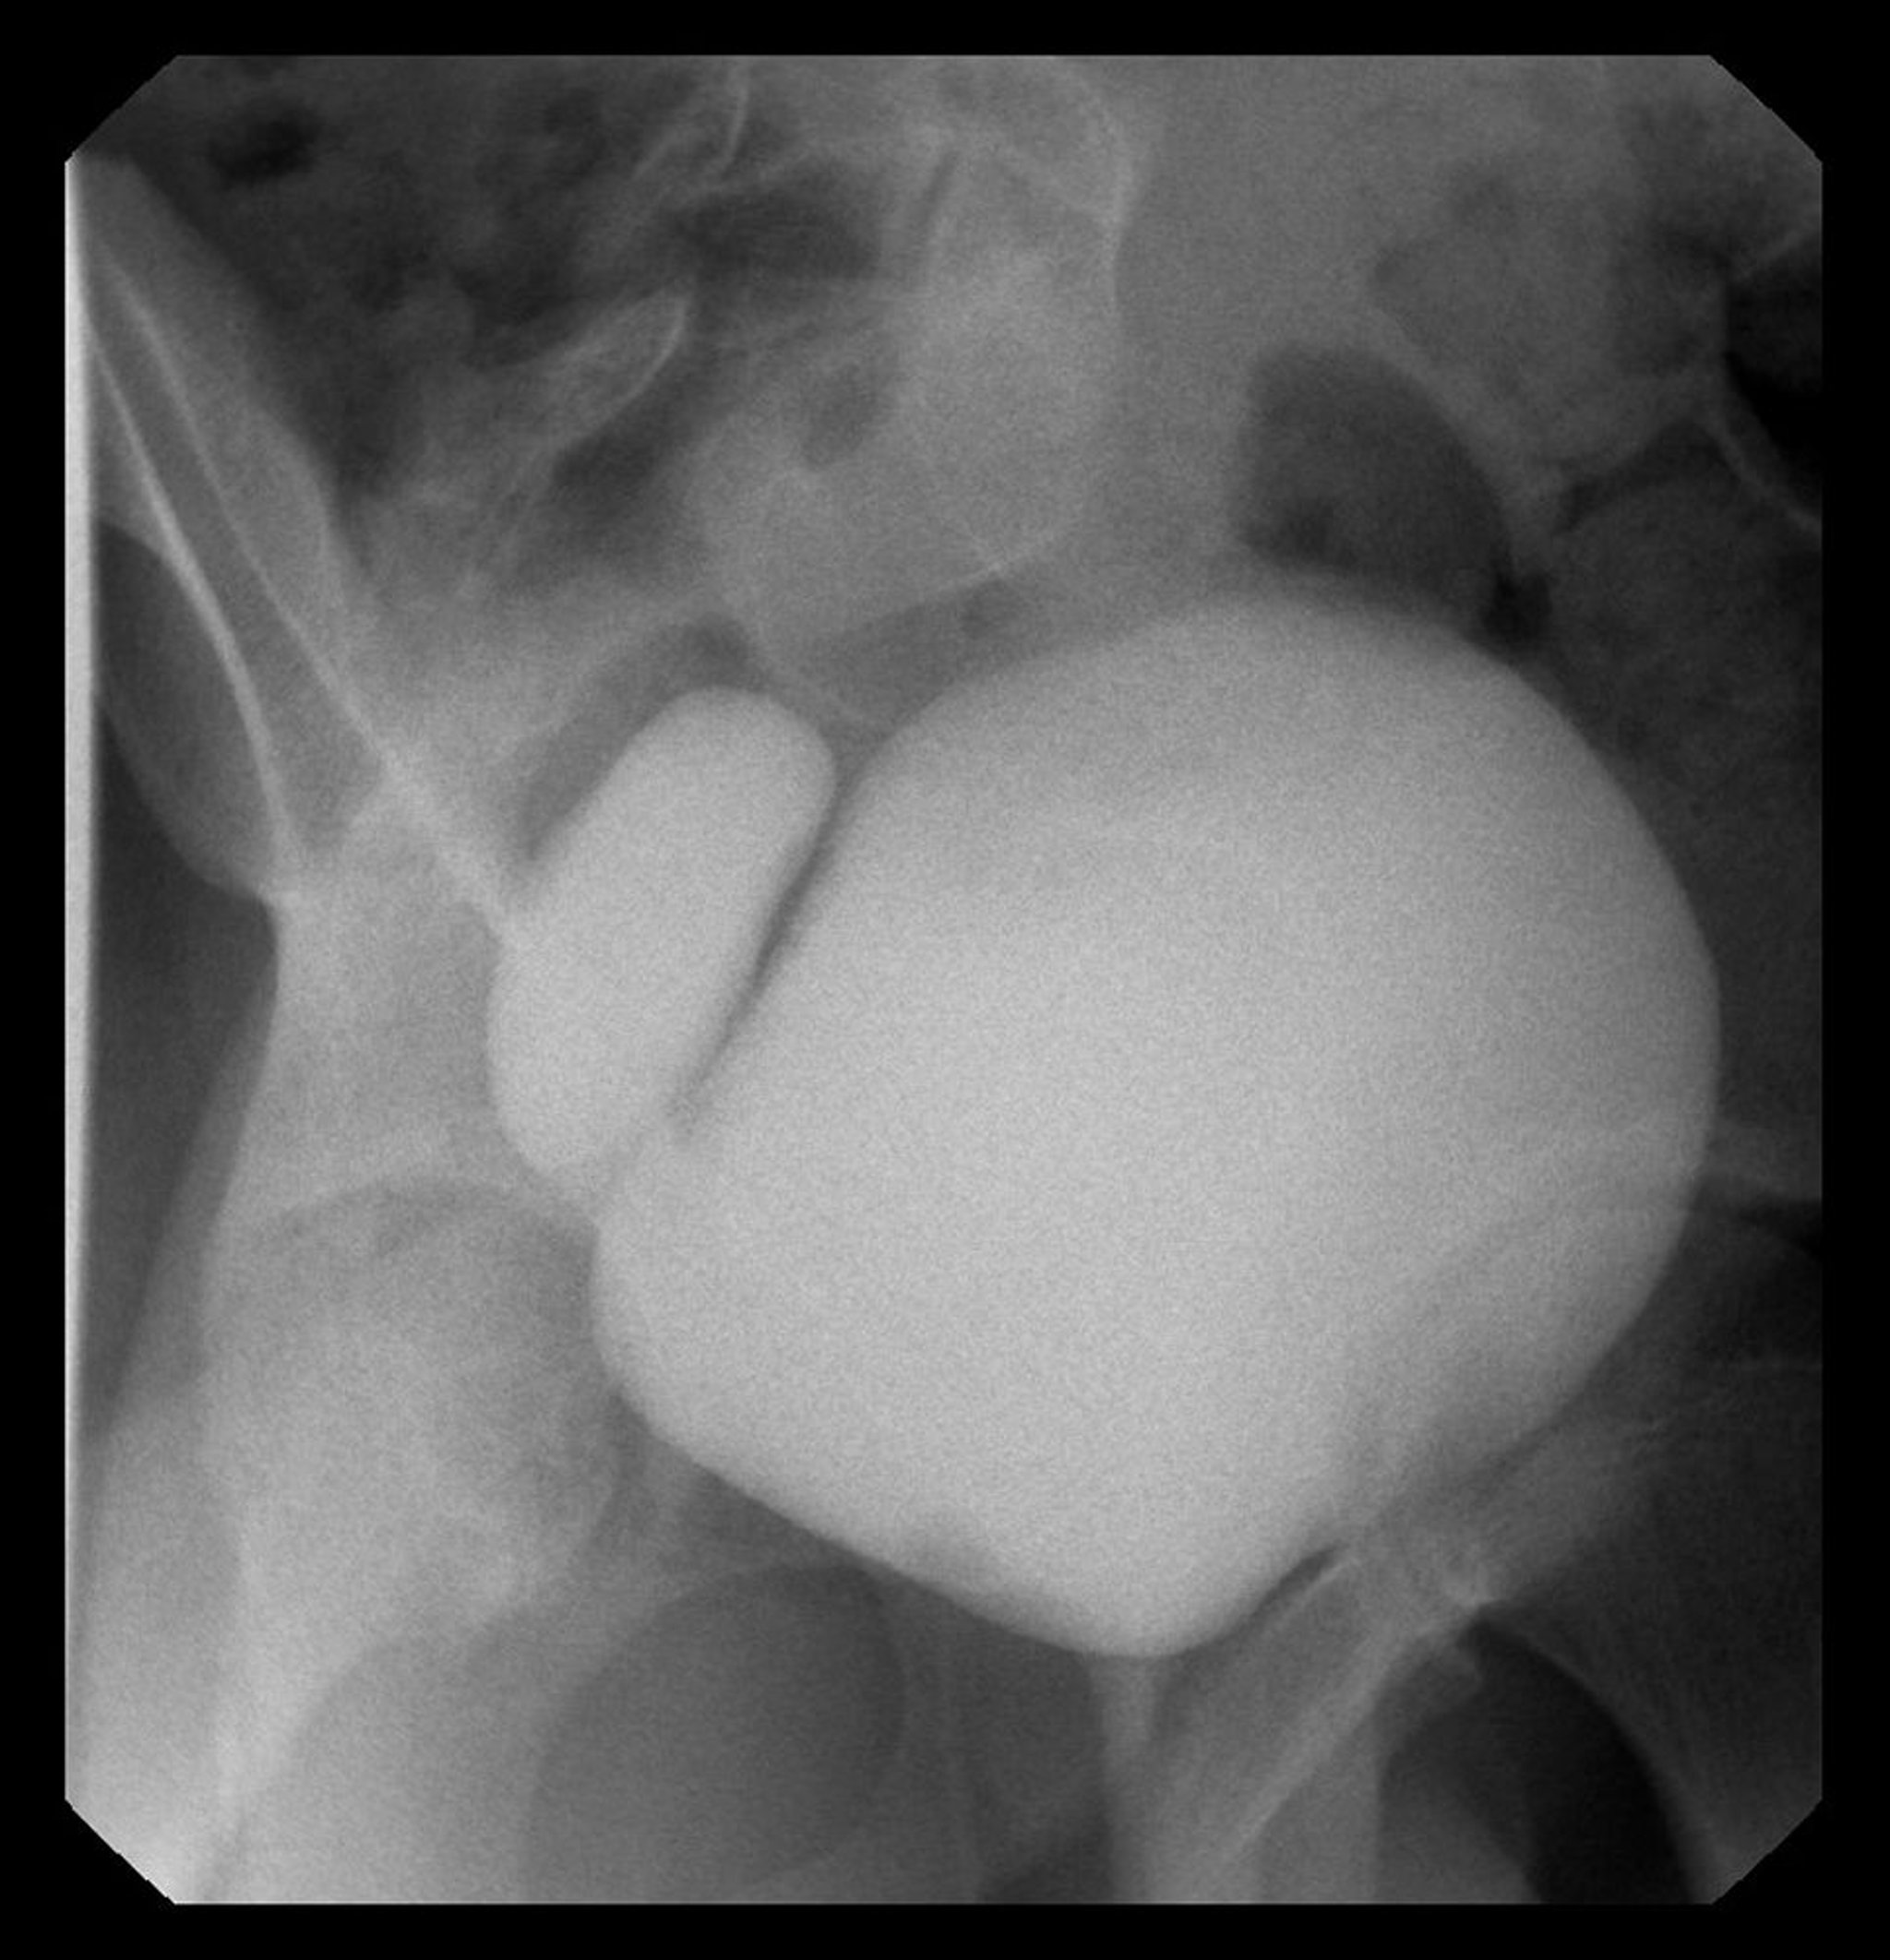

На этом изображении показана цистограмма с правосторонним дивертикулом мочевого пузыря.